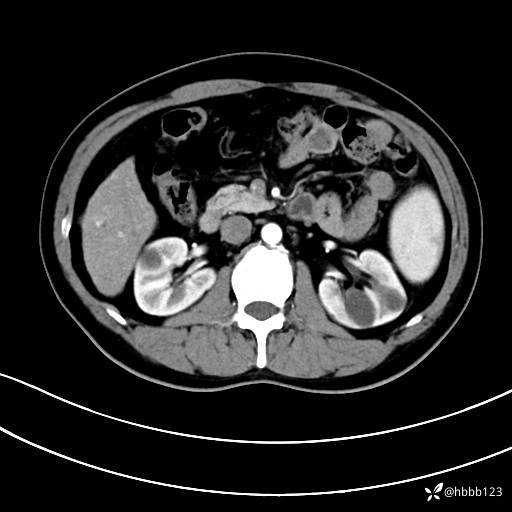

门诊完善上腹部CT平扫+增强。

动脉期: